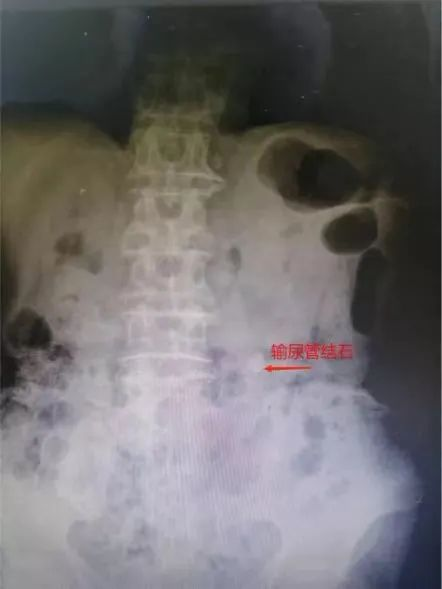

如果把人体比作一个房间,泌尿系统就是一个“下水管道”,其中包括肾脏、输尿管、膀胱以及尿道这几个重要器官,而“尿路结石”就是“下水管道”中的某个部位出现了石头。如果结石长在了输尿管,哪怕只有半公分,都会让人痛不欲生。而来自惠州83岁的翁伯,就因“腰痛”在惠州某医院检查彩超时发现左输尿管上段结石并左肾积水,当地医院建议保守治疗。但保守的治疗效果欠佳,反复的腰痛,严重影响翁伯的生活质量。经患者及其家属多方打听,了解到我院毕学成主任是省内外知名泌尿外科专家,尤其在微创泌尿手术方面造诣颇深,便慕名前来该院泌尿外科就诊。毕学成获悉病情后带领泌尿外科团队认真研究分析病情,经过充分的术前评估后,为患者实施了微创激光碎石手术,成功打通了“下水道”!术后复查结石清除干净,彻底解除了翁伯的“腰痛”问题。出院时,翁伯激动地说:“水龙头开关终于打开了,解决了我多年的困扰,真心为你们医院高超的医疗技术和优质的服务点赞。”

病人术前X光